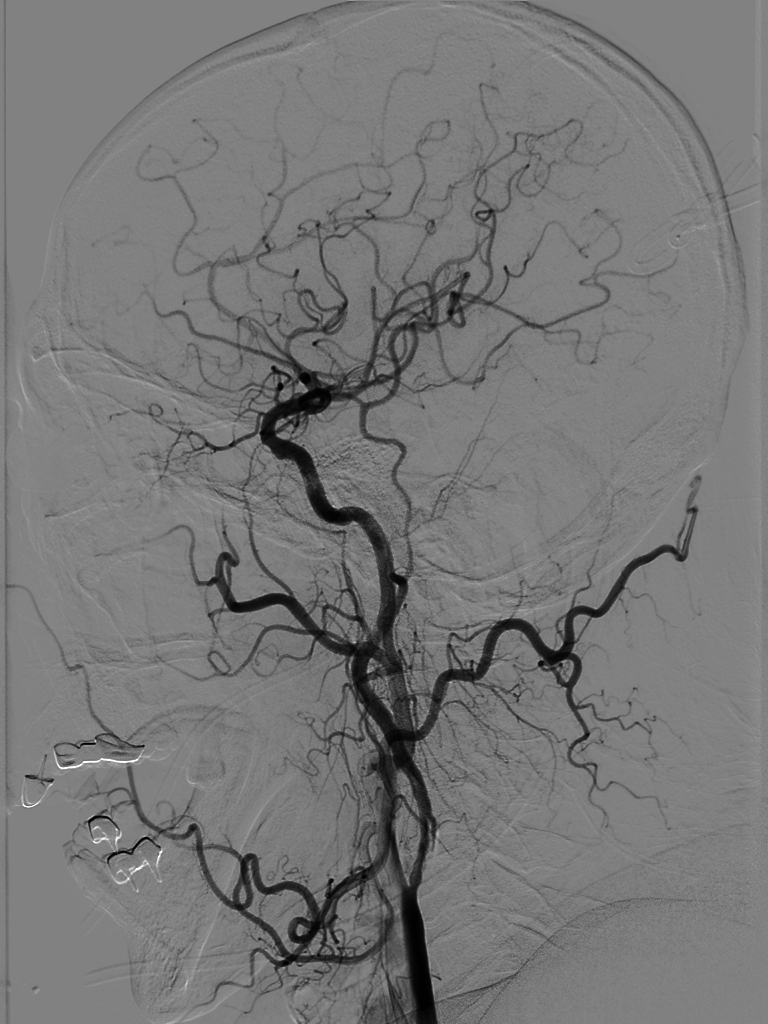

4*20mm Trevo ProVue取栓支架释放,5分钟后抽拉结合取栓,一次取栓,大脑中动脉完全再通。

动脉长鞘怎么置入【沙场点兵 有史可鉴】Trevo ProVue联合Infinity长鞘经桡动脉取栓分享_https://www.jmylbn.com_新闻资讯_第16张

动脉长鞘怎么置入【沙场点兵 有史可鉴】Trevo ProVue联合Infinity长鞘经桡动脉取栓分享_https://www.jmylbn.com_新闻资讯_第17张

大脑中动脉完全再通。